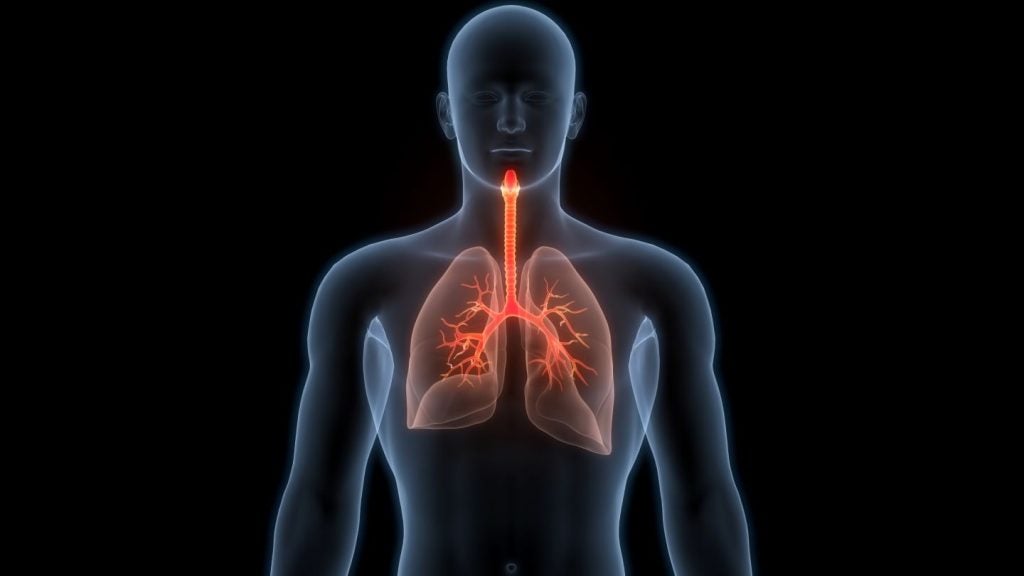

EDX Medical develops rapid pneumonia test for hospital patients

EDX claims the test, which is intended for use in the ICU, provides results for guiding treatment decisions within 60 seconds.

EDX claims the test, which is intended for use in the ICU, provides results for guiding treatment decisions within 60 seconds.